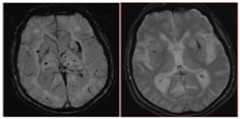

Figure 3.

Microhemorrhage and superficial siderosis

Left: White arrows indicate multiple 1–3mm dark foci in the right inferior temporal and occipital lobes, typical of the appearance of mH. Red arrow indicates inferior sagittal sinus, and yellow arrow indicates susceptibility artifact, as vascular structures and artifacts can sometimes mimic the appearance of mH and siderosis. Right: White arrows indicate curvilinear dark sulci in the right frontal lobe, typical of the appearance of superficial siderosis. Both images were acquired at 1.5T with a 2D long TE (30ms) GRE sequence.